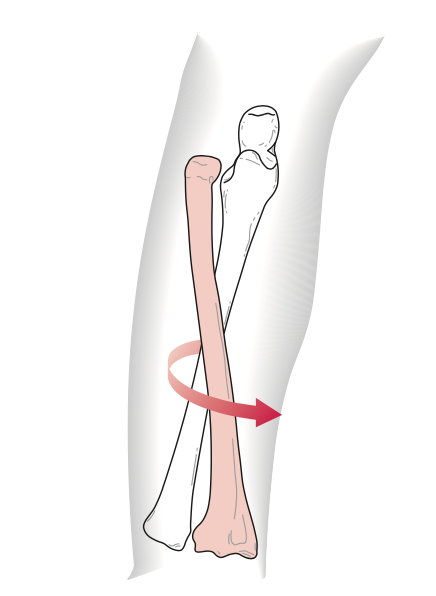

Các vận động cẳng tay:

Sự kết hợp hai khớp quay trụ cho động tác Sấp và Ngửa (thật ra là xoay trong và xoay ngoài).

Tầm vận động: Ngửa 80 – 90 độ, Sấp 70 – 90 độ